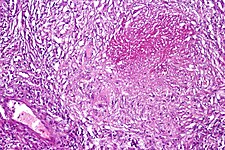

Pulmonary tuberculosis characterized by granulomatous inflammation with necrotizing epithelioid granulomas. Low power view. H&E stain.

Pulmonary tuberculosis featuring necrotizing granulomas, H&E stain.

Pulmonary tuberculosis featuring necrotizing granulomas, high power view, H&E stain.